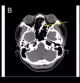

Una vez allí, los médicos quisieron saber de dónde procedía el dolor exactamente, por lo que le realizaron una prueba de radiografía. Para su sorpresa, encontraron la causa del dolor del hombre: tenía todo tipo de objetos metálicos en su interior, con medidas desde dos milímetros hasta diez centímetros, tal y como afirman los medios locales.